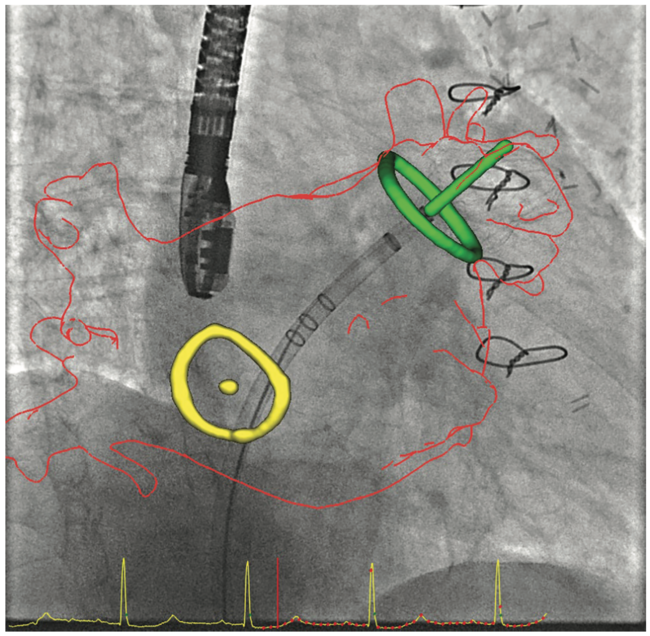

GE HealthCare’s fusion system helps by allowing us to fuse the live fluoroscopy to the pre-procedure CT scan. Most of the time, before walking into the room for a TAVR, for example, you already will have a fairly good understanding of how valve alignment is going to take place, because of the pre-procedure imaging. Fusion technology plus additional software that we use allows us to determine the angulation and directs how to position our detector so we have the best views for performing TAVR. The fusion software also allows us to further minimize the dose of radiation during the procedure, particularly in complex procedures, using distal protection such as the Sentinel™ system to protect the cerebral circulation in patients who are undergoing TAVR.

Praveen Mehrotra, MD: There are several echocardiographic technologies, recently developed, that help to solve some of the imaging challenges during structural heart procedures. First and foremost is the need for outstanding 3D volumetric and multiplanar imaging with high spatial resolution and frame rates. We use live 3D imaging to help guide certain procedures and to obtain critical measurements prior to the start of the procedure, usually for device sizing. There is a new technology called 4D Markers (GE HealthCare), which we can place on 2D and 3D echo images. The interventional cardiologist can view the 4D Markers onscreen and use them as a target, so he or she knows where we are asking them to direct a wire or catheter without the echocardiologist having to verbalize it or struggle to communicate that information. The markers exist in 3D space, so we can see them in multiple views simultaneously. Another useful technology called View-X (GE HealthCare) places the fluoroscopic image adjacent to the TEE image on the echo machine. This technology allows me to visualize the procedure from the standpoint of the interventionalist, integrate fluoroscopic and echocardiographic data, and anticipate what information will be needed next by the interventional cardiologist or surgeon.

We are also starting to use fusion technology. There are several different types of fusion imaging technology currently available on the market; one recently released fusion technology is CT-Echo Fusion (GE HealthCare) that fuses previously acquired CT data to the live 3D echo image. Echocardiography can suffer due to dropout from calcification or devices. This fusion technology allows us to integrate CT imaging that we already utilize for pre-procedural planning of structural heart procedures and integrate that with the echocardiographic images obtained on the day of the procedure. These fusion technologies are currently evolving and may prove to be very useful in complex structural heart procedures where echocardiography alone may not be sufficient.